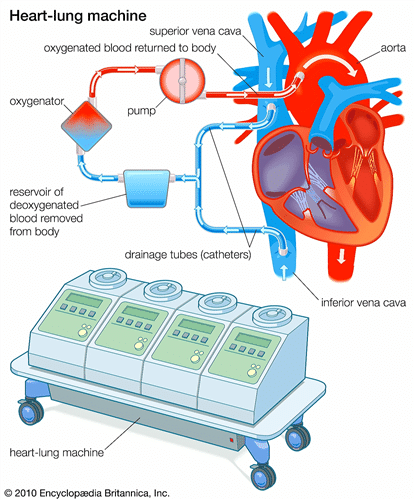

1- تقنية استخدام جهاز المضخة القلبية (ماكينة القلب الصناعي )

يساعد جهاز القل بالصناعي في نقل الدم والأكسجين إلى جميع أنحاء الجسم بدلًا من القلب أثناء العملية حيث يكون القلب لا ينبض، وبعد انتهاء العملية يقوم الطبيب بفصل الجهاز ويعود القلب للعمل مرة أخرى كما كان.

- يتم تركيب جهاز المجازة القلبية إذا كانت التقنية المستخدمة في العملية هي تقنية المضخة القلبية.